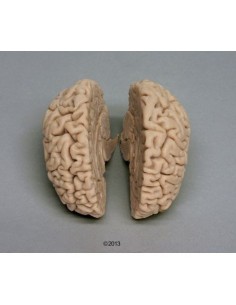

Dal cranio in 22 parti con incastri magnetici ai modelli di colonna vertebrale, da quelli di articolazioni a quelli di cuore, ogni pezzo della nostra collezione è progettato per un’immersione totale nello studio dell’anatomia umana. I nostri modelli, realizzati tramite scansioni di ossa vere, garantiscono un’esperienza tattile autentica e una fedeltà di peso quasi identica agli originali.

Essenziali per studenti e professionisti, i nostri modelli anatomici sono strumenti didattici che permettono di osservare le strutture anatomiche con precisione, eliminando la necessità di dissezioni o studi invasivi. Sono inoltre utili per spiegare ai pazienti le patologie, rendendo la comunicazione più efficace e risparmiando tempo prezioso.